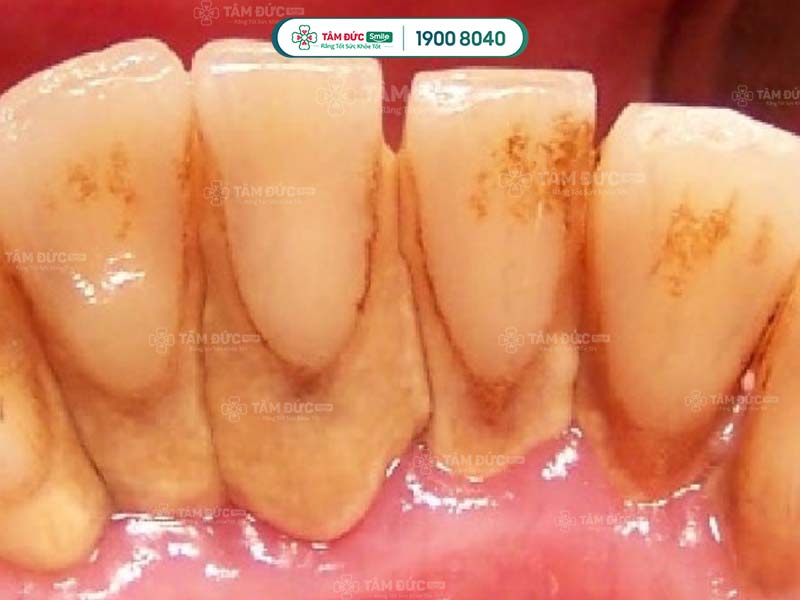

Cao răng tích tụ lâu ngày sẽ gây ra các bệnh lý như: Sâu răng, viêm nướu, tụt nướu, mòn men răng, viêm nha chu,... Do đó, cạo cao răng thường xuyên giúp Quý khách ngăn chặn vi khuẩn phát triển, giảm nguy cơ mắc phải các bệnh lý răng miệng.

cạo cao răng để ngăn ngừa các bệnh răng miệng

cạo cao răng để ngăn ngừa sâu răng và viêm nhiễm